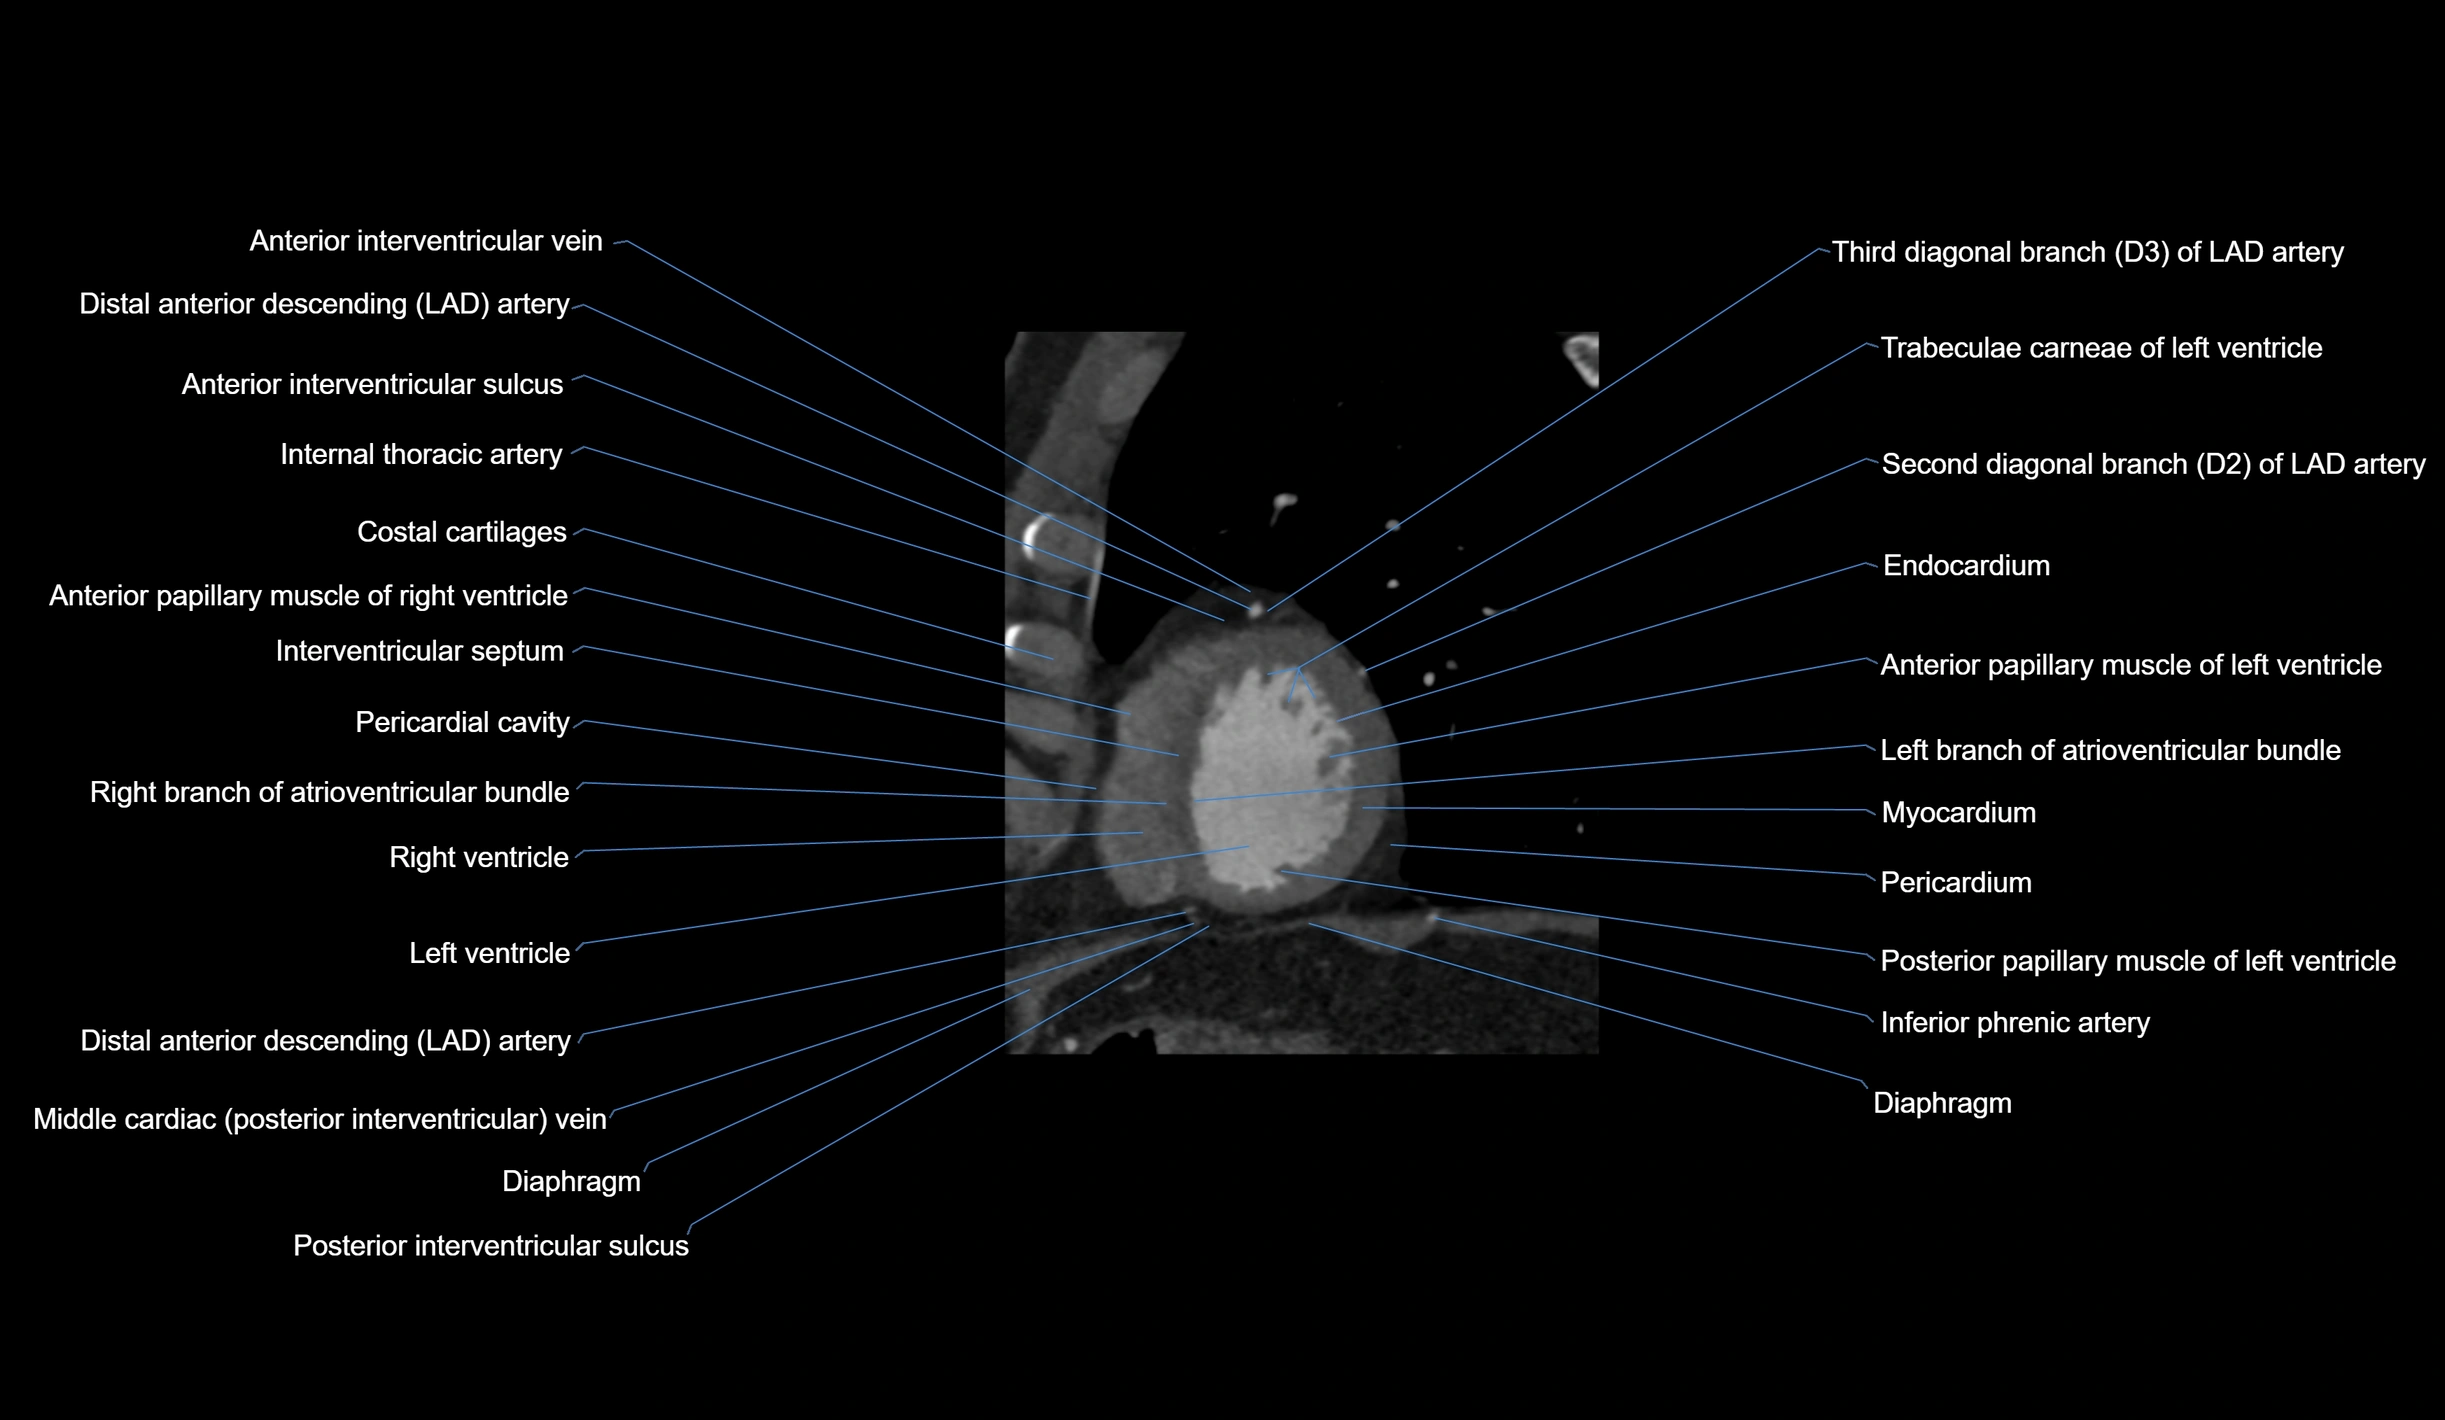

- Distal left anterior descending artery (dLAD)

- Left anterior descending artery (LAD)

- Left branch of atrioventricular bundle

- Left ventricle

- Right branch of atrioventricular bundle

- Right ventricle

- Third diagonal branch (D3) of LAD

- Second diagonal branch (D2) of LAD

- Trabeculae carneae

- Endocardium

- Myocardium

- Pericardium

- Pericardial cavity

- Posterior interventricular sulcus

- Anterior interventricular sulcus